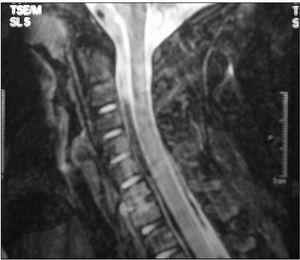

Las técnicas diagnósticas de imagen empleadas se detallan en la tabla 2. La radiografía convencional se realizó en 15/20 pacientes, mostrando alteraciones en diez, siendo el hallazgo más frecuente la disminución del espacio intervertebral (fig. 1). La gammagrafía mostró hipercaptación del radiofármaco en 14 de los 15 casos en que se realizó (fig. 2). La resonancia magnética (RM) se realizó a 15 de los 20 pacientes. La lesión predominante fue la afectación del disco intervertebral con erosiones de los platillos vertebrales adyacentes. En al menos 5 pacientes se objetivaron lesiones de partes blandas y abscesos paravertebrales (fig. 3). En 2 pacientes la afectación vertebral fue múltiple (dos o más espacios), habiéndonos referido en la localización al más afectado. Se realizó una tomografía computarizada (TC) en 6 casos, si bien uno de ellos fue abdominal por síntomas de estreñimiento y dolor abdominal. En 3 niños se realizó punción del disco intervertebral guiada por TC que no aportó aislamiento del germen en ningún caso.

Figura 3.RM de una paciente con espondilodiscitis cervical C6-C7 con absceso paravertebral.

En nuestra serie el diagnóstico definitivo se estableció con las pruebas de imagen que se detallan en la tabla 2. A 15 pacientes se les realizó una radiografía simple de columna, siendo ésta normal en 5 pacientes y mostrando una inespecífica rectificación de la lordosis en dos. En 4 de los 5 pacientes en los que la radiografía fue normal se realizó una RM y todas presentaron signos compatibles con espondilodiscitis, y el quinto caso tenía una gammagrafía que mostraba un aumento de captación en L5-S1. La RM fue diagnóstica en todos los casos realizados. Coincidimos con otros autores en que esta técnica permite establecer un diagnóstico precoz cuando los signos clínicos son difíciles de interpretar, y debería ser considerada como la prueba de imagen de elección cuando se sospecha el diagnóstico de espondilodiscitis, sobre todo en fases precoces donde otras pruebas pueden ser negativas5,16,18. Además permite diagnosticar la presencia de abscesos paraespinales que se han descrito hasta en el 37 % de los casos1, e incluso algún autor habla del 75 %2, así como complicaciones que involucren las raíces nerviosas. Las pruebas de medicina nuclear son muy sensibles y ayudan bastante al diagnóstico, localizando el lugar de la lesión, aunque son poco específicas (78 % para la gammagrafía con 99Tc) y pueden retrasar el diagnóstico5 y la TC, aunque aporta una adecuada información, supone una importante carga de radiación que hace que en la actualidad se esté abandonado como técnica diagnóstica a favor de la RM. Tiene su indicación principal cuando se precisa realizar una punción del disco1,5.